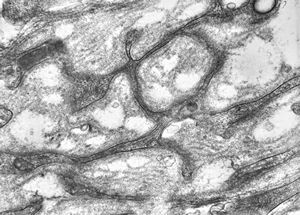

rabbit spinal cord trauma